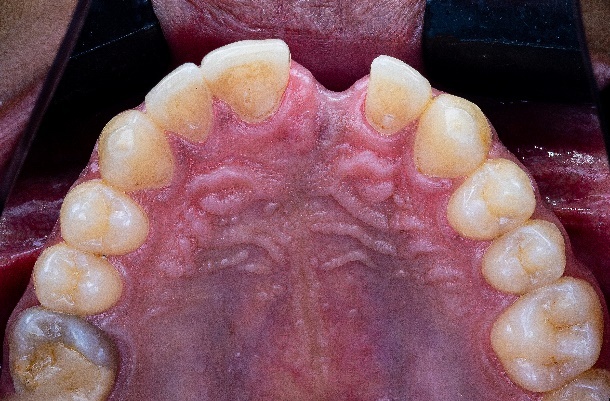

The patient, a 35-year-old male, sought treatment six months after losing his anterior tooth (21) due to trauma. Clinical examination revealed soft tissue depression in the edentulous area, while CBCT imaging showed insufficient horizontal bone width (<4mm) in the region, with normal vertical bone height, adjacent teeth, and occlusal relationships, the patient has high aesthetic demands. (Fig2,3,4,5)

The latest intraoral scanner, the Elite from Shining 3D, was used to quickly capture stl data of both the upper and lower jaws, as well as gingival morphology and proportions relative to adjacent teeth (Fig 6). Additionally, the MetiSmile face scanner from Shining 3D, combined with digital smile design, was utilized to determine the morphology and incisal edge position for the future restoration (Fig 7).